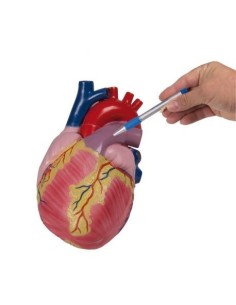

Du crâne en 22 parties à verrouillage magnétique aux modèles de colonne vertébrale, des modèles d'articulation aux modèles de cœur, chaque pièce de notre collection est conçue pour une immersion totale dans l'étude de l'anatomie humaine. Nos modèles, réalisés à partir de scans d'os réels, garantissent une expérience tactile authentique et une fidélité de poids presque identique aux originaux.

Indispensables aux étudiants comme aux professionnels, nos modèles anatomiques sont des outils pédagogiques qui permettent d'observer les structures anatomiques avec précision, en évitant les dissections ou les études invasives. Ils sont également utiles pour expliquer les pathologies aux patients, ce qui rend la communication plus efficace et permet de gagner un temps précieux.